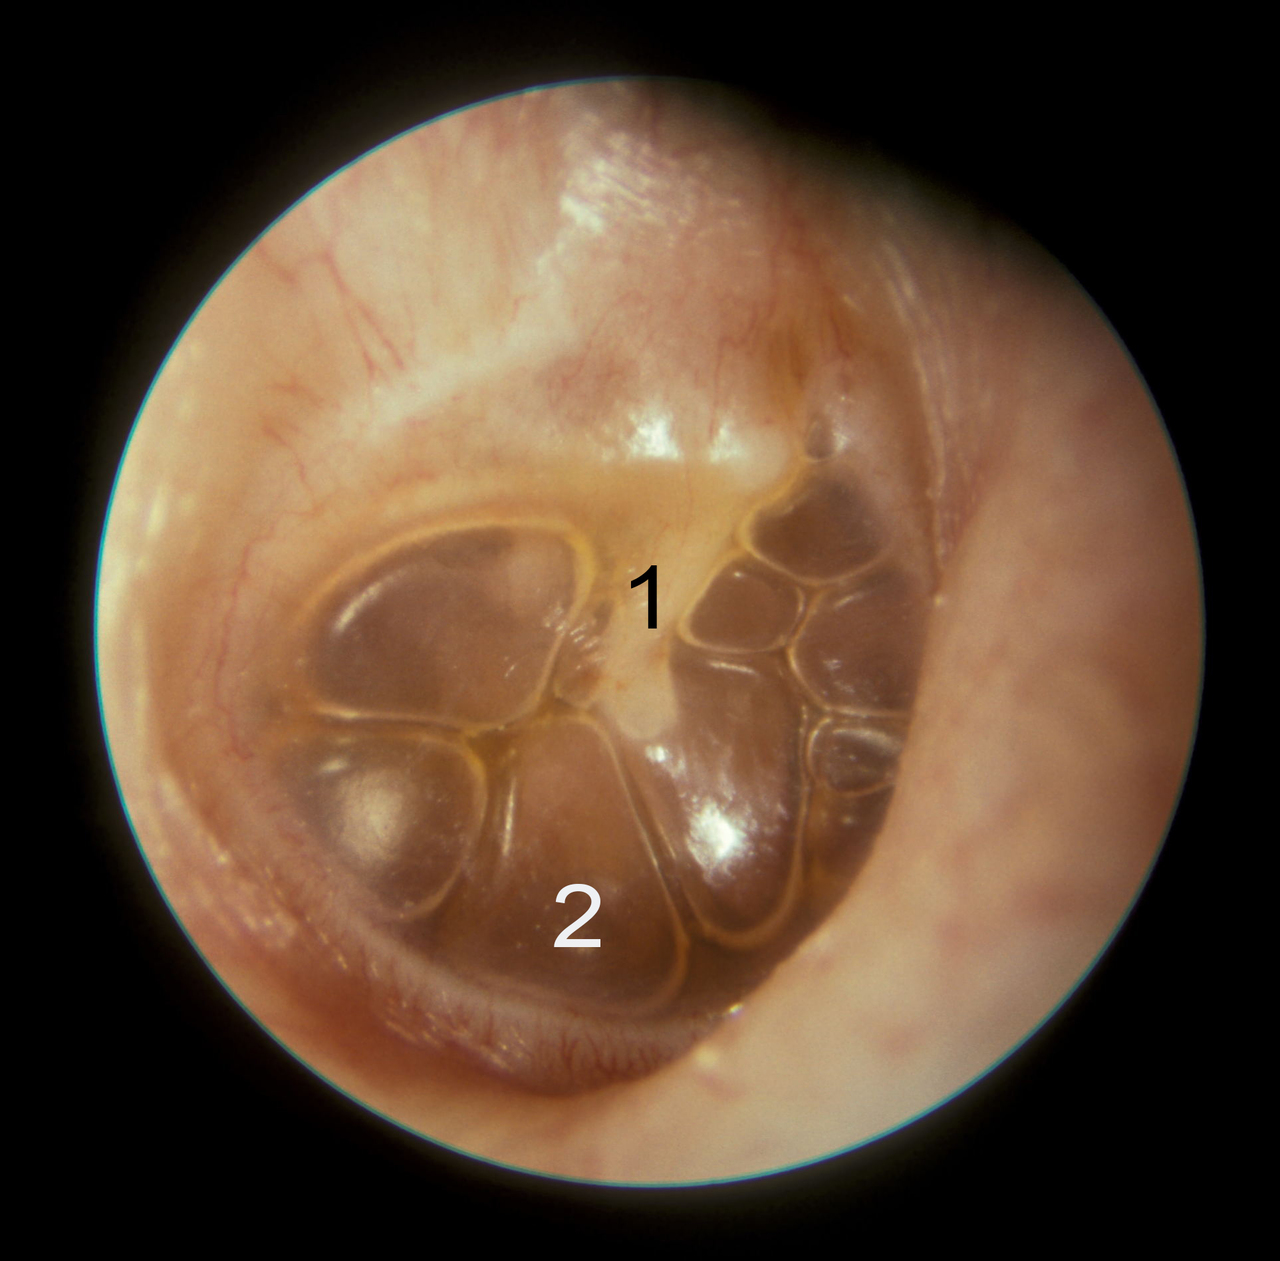

Voici le tympan gauche

Question 6 : Qu’en pensez-vous ?

C’est l’osselet qui s’appelle le marteau ou malleus

L’enclume (ou incus) ne se trouve pas dans l’épaisseur du tympan mais dans la caisse du tympan

C’est une bulle d’air derrière le tympan, qui est visible car il y a du liquide

Ici, le tympan n’est pas inflammatoire ni bombant. Le triangle lumineux est bien visible et le relief du marteau également : il n’y a pas d’argument pour une OMA

La présence de liquide et de bulle rétrotympanique est pathognomonique d’une OSM

Ce tympan permet de diagnostiquer une OSM. Mais puisque c’est le premier examen il faut d’abord faire un contrôle à 3 mois avant d’envisager un traitement.